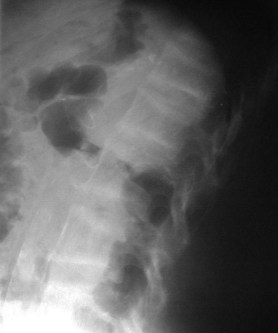

SIGNO DE LA SEMILUNA

Línea curva subcondral radiolucente cuya localización típica es la cara anterolateral de la cabeza femoral (aunque puede ocurrir en otras localizaciones) y corresponde a necrosis avascular. Esta lesión deriva en colapso de la superficie articular de la cabeza femoral.

En la imagen, este signo (flechas) en un niño con enfermedad de Perthes.